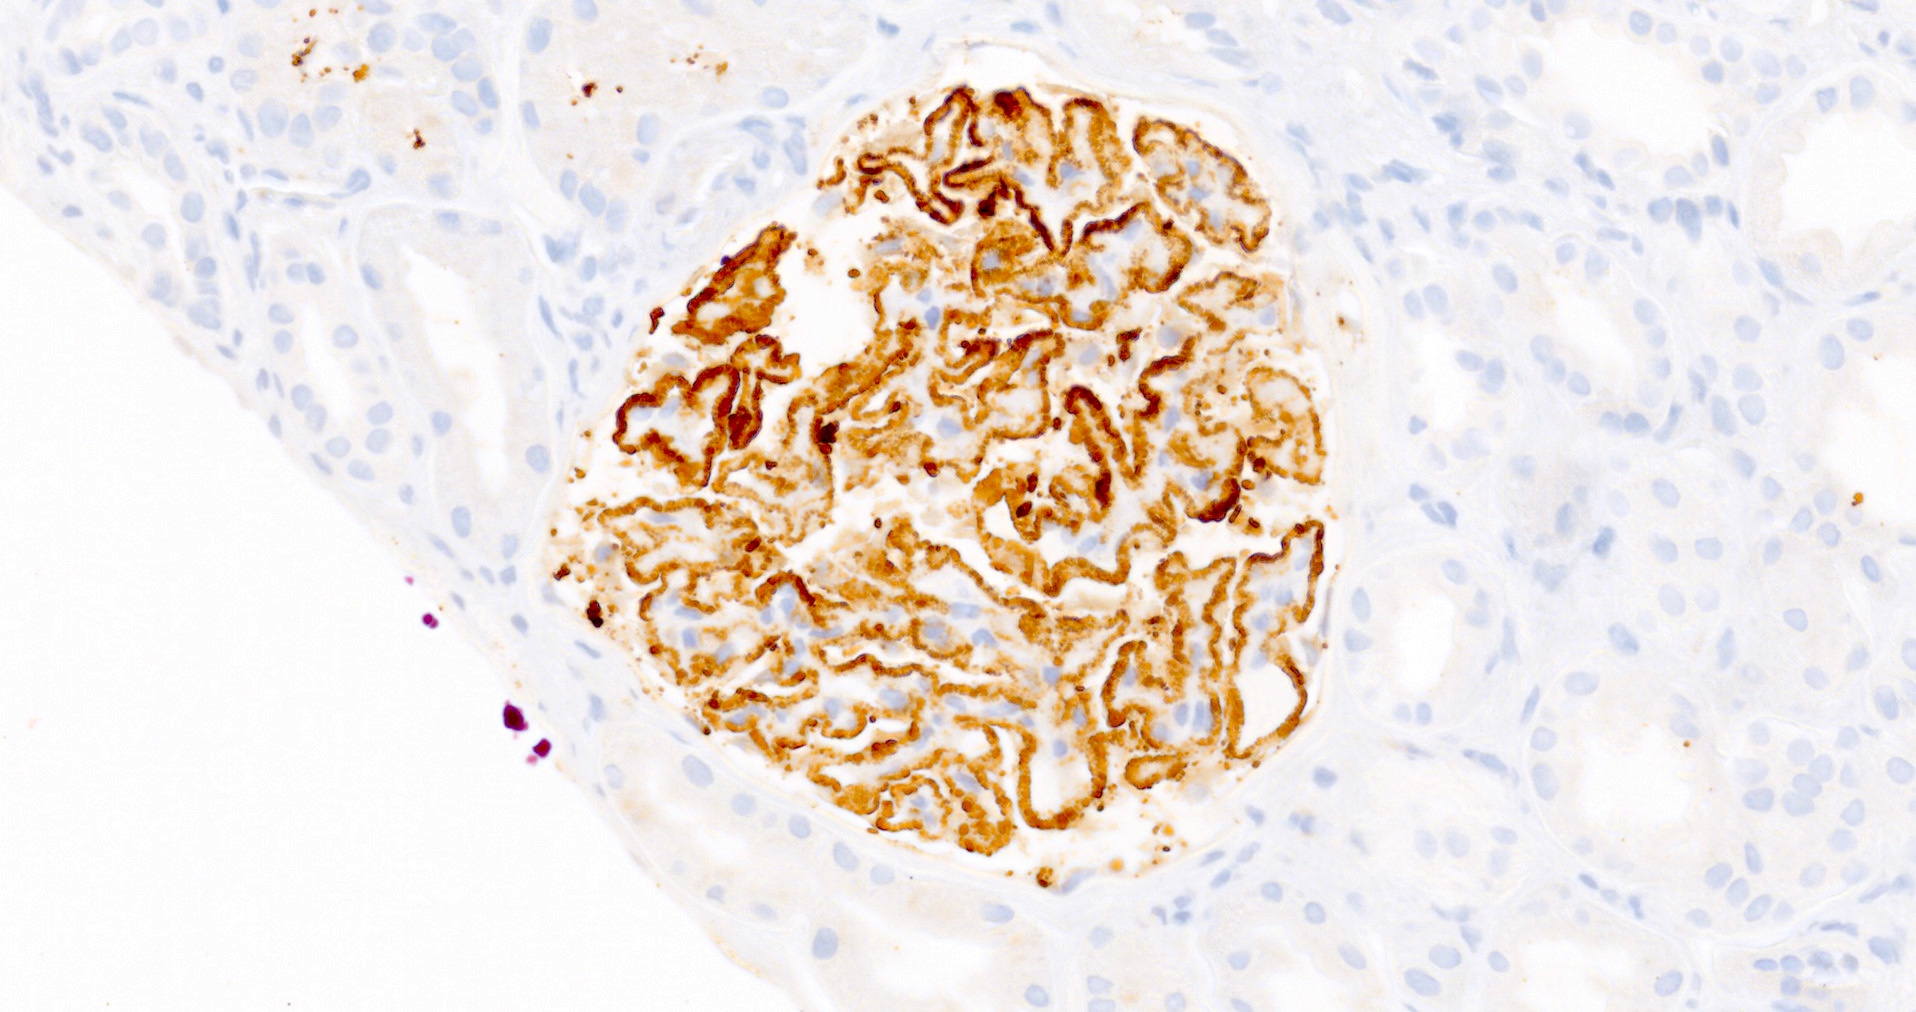

Microscopic (histologic) images

Microscopic (histologic) description

- Glomeruli may appear entirely normal in early disease (stage 1)

- Thickening of glomerular basement membrane

- Subepithelial spike formation or vacuolated appearance on PAS or Jones silver stain (Colvin: Diagnostic Pathology - Kidney Diseases, 2nd Edition, 2015, Zhou: Silva's Diagnostic Renal Pathology, 2nd Edition, 2017)

Positive stains

- PLA2R and IgG4: intense global and granular staining of glomerular basement membrane (Appl Immunohistochem Mol Morphol 2021;29:414)